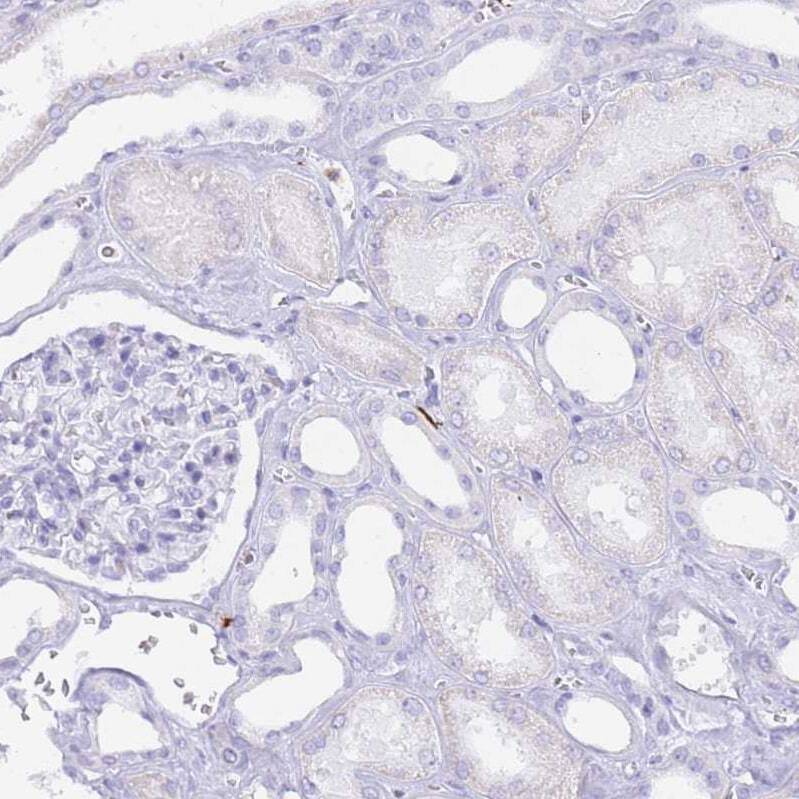

- Immunohistochemical analysis of HERC1 in human kidney using HERC1 Polyclonal Antibody (Product # PA5-62033) shows no cytoplasmic positivity in cells in tubules as expected.

- Submitted by

- Invitrogen Antibodies (provider)

- Main image

- Experimental details